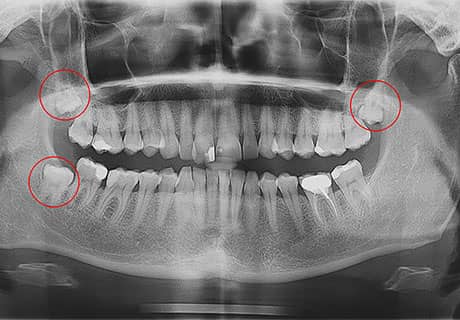

Зуби мудрості не виросли повністю

Атипове розташування зуба